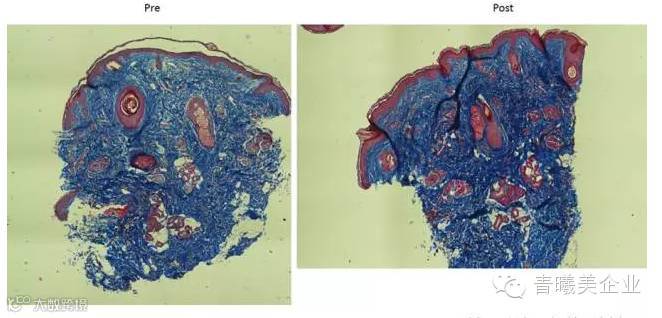

两次治疗后三个月胶原蛋白(蓝色)密度的全面增加

超级射频:面部疗效